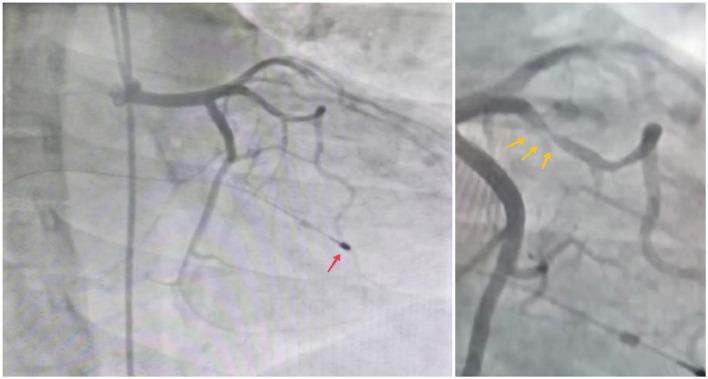

Complete heart block (CHB) is a disruption in electrical impulses to travel from atria to ventricles and can rarely be caused by myocardial bridging (MB), where cardiac tissue compresses a coronary artery during systole. The incidence of MB ranges from 0.5 % to 16 % in coronary angiography patients. This case report presents a 30-year-old female presented with dizziness, shortness of breath, and chest pain, diagnosed with third-degree AV block. Echocardiography revealed interventricular septal thickening and mild mitral regurgitation. Coronary angiography identified myocardial bridging in the mid LAD artery causing significant systolic stenosis. After ruling out reversible causes, a dual-chamber permanent pacemaker was implanted due to persistent heart block. The patient remained stable postprocedure, with decreasing cardiac biomarkers, and was discharged symptom-free with a follow-up appointment scheduled. MB can lead to serious cardiovascular events, including myocardial infarction and CHB. Clinicians must recognize the risks associated with MB and maintain a high suspicion for CHB to ensure timely management. Further studies are needed to clarify the CHB-MB relationship and improve patient outcomes.

摘要